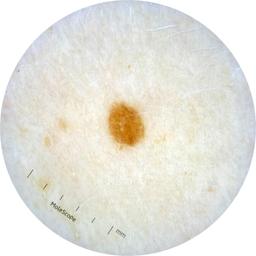

ISIC_2261268

2061 x 2061

acquisition_day 307

age_approx 50

anatom_site_1 Trunk

anatom_site_2 Posterior trunk

anatom_site_general posterior torso

diagnosis_1 Benign

diagnosis_confirm_type single image expert consensus

image_type dermoscopic